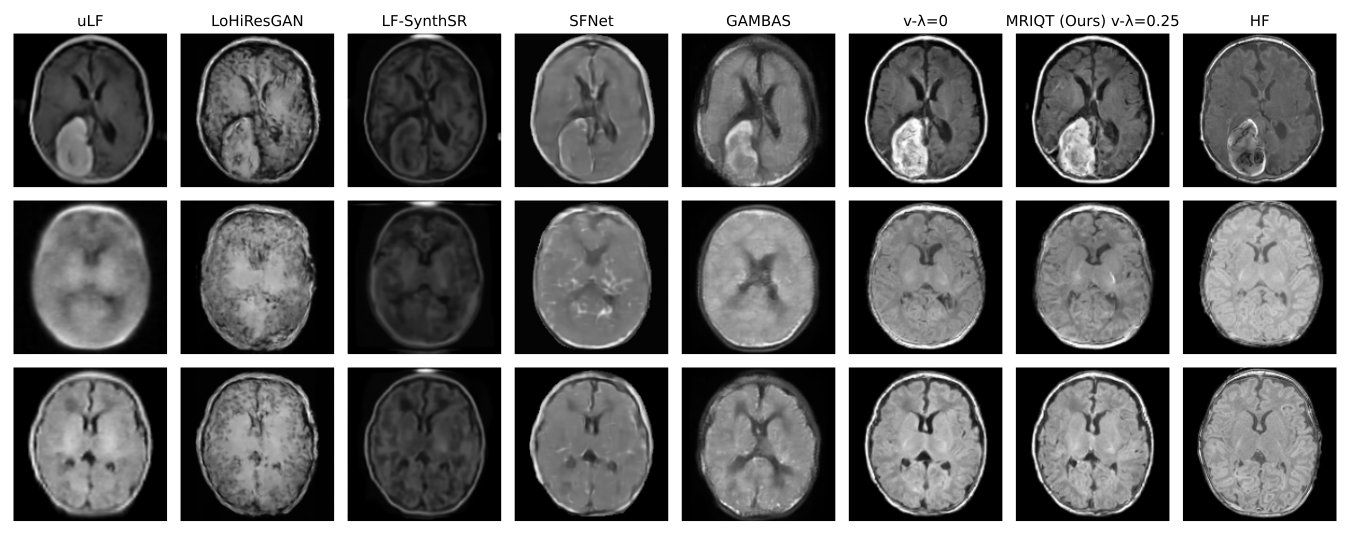

Refer to caption

Fig. 3: Qualitative comparison of 3 samples on the axial view on IQT. Left to right: ULF, LoHiResGAN [Islam2023improving], LF-SynthSR\ddagger [iglesias2022quantitative], SFNet\dagger [Tap_SuperField_MICCAI2024], GAMBAS\dagger [baljer2025gambas], Our base model, Ours, reference HF scan. [(\dagger) trained on T2w-scans, (\ddagger) requires both T1w and T2w scans for testing.]

3.4 Qualitative Analysis

Figure 3 compares uLF, SoTA, and MRIQT reconstructions. Competing GAN-based models (e.g., LoHiResGAN, SFNet) tend to oversharpen edges or hallucinate fine structures, while MRIQT consistently restores cortical boundaries and deep-gray matter contrast without introducing artifacts. MRIQT also preserves pathological features such as hemorrhagic lesions and ventricular enlargement, aligning closely with HF image. The denoising smoothness and texture recovery further confirm that diffusion-based IQT generalizes effectively across unseen pathologies.